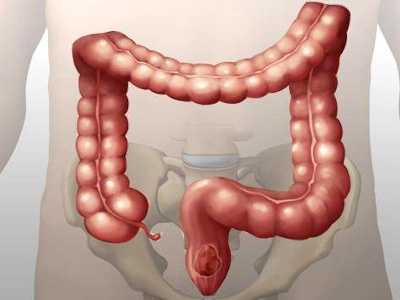

Толстокишечные придатки (processus epiploicae, или жировые подвески)

Представляют собой небольшие выпуклости толстой кишки, стенка которых состоит из серозного и субсерозного слоя, заполненные жировой тканью. Для хирурга важно, что в них содержатся терминальные ветви брыжеечных артерий и их хирургического удаления следует избегать.

Epiploic appendages — жировые привески — перитонеальные мешки на серозной оболочке толстой кишки расположенные на сосудистой ножке. Состоят из жировой ткани и кровеносных сосудов, обычно имею длину 0,5-5см. Самыми крупными являются привески сигмовидной кишки и могут располагаться группами около 100. Как правило, привески видны на КТ, только если они воспалены и /или окруженный жидкостью.

Аппендажит представляет собой слабовыраженное воспаление одного из многочисленных отростков сальника, которые в количестве 50-100 штук располагаются вдоль толстого кишечника. В основе патогенеза лежит перекрут крупного отростка или спонтанный тромбоз отводящей вены приводящие к ишемии с последующим некрозом.

Патология жировых подвесков толстого кишечника (appendices epiploicae), по данным разных статистик, составляет 0,09-0,3% острых заболеваний брюшной полости [1, 2, 4, 5]. Чаще всего воспаление appendices epiploicae возникает из-за его перекрута. Чем длиннее подвеска, тем выше вероятность ее перекрута. Средняя длина подвески составляет 3 см, однако может достигать 15 см и более [2, 3, 5]. В дистальных отделах толстой кишки число подвесок и длина постепенно возрастает. По данным различных статистик, при заболевании жировых подвесков заворот был обнаружен у 31,4% больных, тромбоз сосудов и инфаркт — у 15,6%, гангрена — у 19,7%, острое воспаление и нагноение жировых подвесков у — 18,6% [5]. По сведениям рада авторов, число пораженных сальниковых отростков колеблется от 1 до 12 [1, 2, 3, 5]. Летальность при заболеваниях сальниковых отростков достигает 1,6% [2, 3, 5].